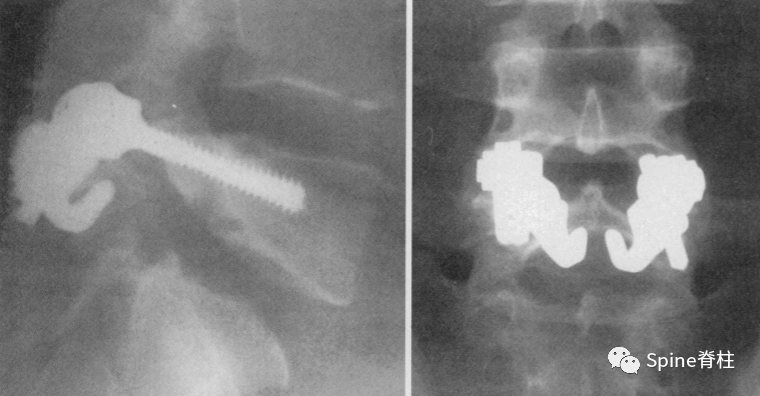

右侧为进展期峡部裂,左侧为早期峡部裂,右侧图片是支具固定7个月后愈合

图:腰5双侧峡部裂,右侧为最早期,左侧为晚早期